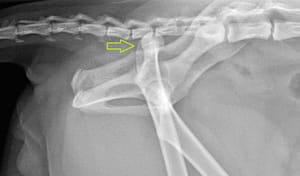

De foto hieronder laat een heupluxatie van een kat zien na een auto ongeluk.